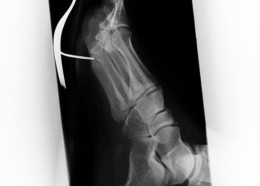

Чудни ренгенски снимки